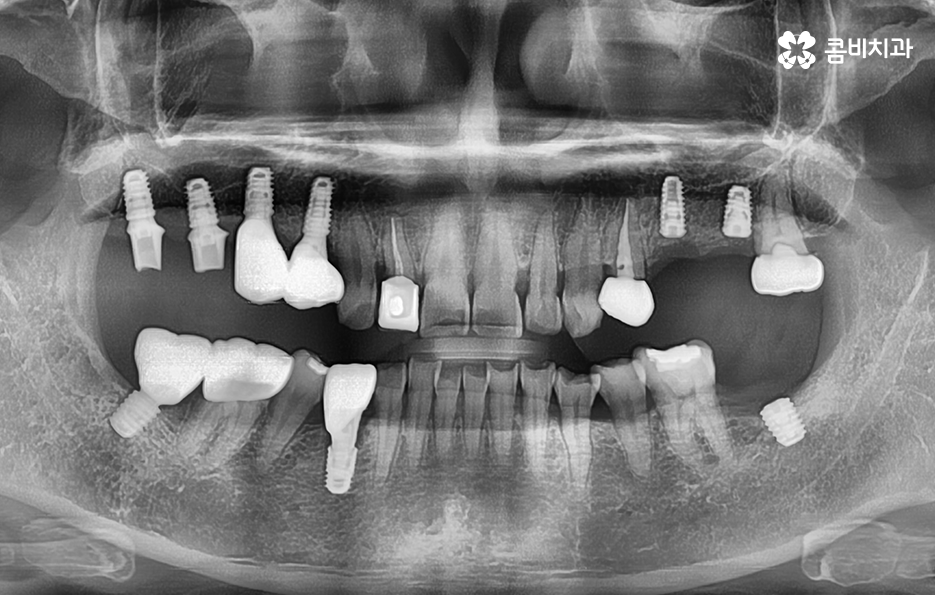

우리가 보편적으로 생각하게 되는 임플란트 치료기간의 경우 치아 하나를 상실하고 임플란트를 1:1로 치료할 때 예상 기간에 대해서 고려하게 되는 경우가 기본적인 접근 방법이라면 실질적으로 치과에서 임플란트를 하게 되는 연령대를 보더라도 보통 50대에서 60대 이후에 치아를 상실하게 되는 환자분들이 급증하기 때문에 위 사진의 사례처럼 여러 치아를 상실하고 임플란트를 식립하게 되는 경우도 많을 거예요

물론 임플란트의 치료 계획에 따라 환자분들의 치료기간도 차이가 있겠지만 보편적으로는 임플란트를 여러개 식립한다고 해서 단순히 더 임플란트의 치료기간이 오래 걸리기 보다는 동시에 임플란트를 식립해도 임플란트 치료기간에서 중요한 골유착 기간은 비슷하기 때문에 식립 개수만큼 치료기간이 비례해서 늘어난다고는 볼 수는 없을 거예요

또는 식립 위치에 따라서 좌, 우 부분적으로 임플란트가 모두 필요한 경우 한 번에 모두 식립을 할 경우 식사가 제한이 되기 때문에 한 쪽 먼저 치료하고 반대쪽을 치료하는 경우가 많아 총 기간은 치료 계획에 따라 차이가 있을 수 있어요.